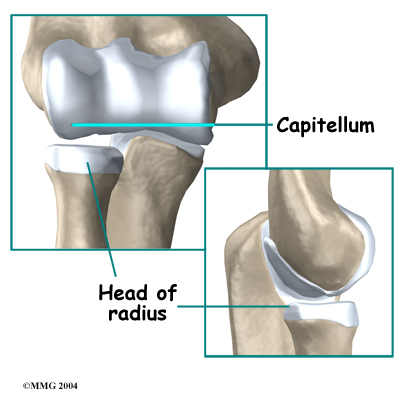

The elbow itself is essentially a hinge joint, meaning it bends and straightens like a hinge. But there is a second joint where the end of the radius (the radial head) meets the humerus. The knob on the end of the humerus is called the capitellum. The capitellum fits into the cup-shaped end of the radius, also called the head of the radius, or radial head. This joint is complicated because the radius has to rotate so that you can turn your hand palm up and palm down. At the same time, it has to slide against the end of the humerus as the elbow bends and straightens. The joint is even more complex because the radius has to slide against the ulna as it rotates the wrist as well.

There is also an important ligament called the annular ligament that wraps around the radial head and holds it tight against the ulna. The word annular means ring-shaped. The annular ligament forms a ring around the radial head as it holds it in place. This ligament can be torn when the entire elbow or just the radial head is dislocated.

In young children, the annular ligament of the radial head is thin and weak. A sudden pull on the forearm can tear this soft tissue structure. The radial head is pulled down through the tear. The annular ligament slips into the radiohumeral joint and becomes trapped between the two joint surfaces when the arm is let go. This is a radial head subluxation. When the annular ligament is pinched it causes pain.